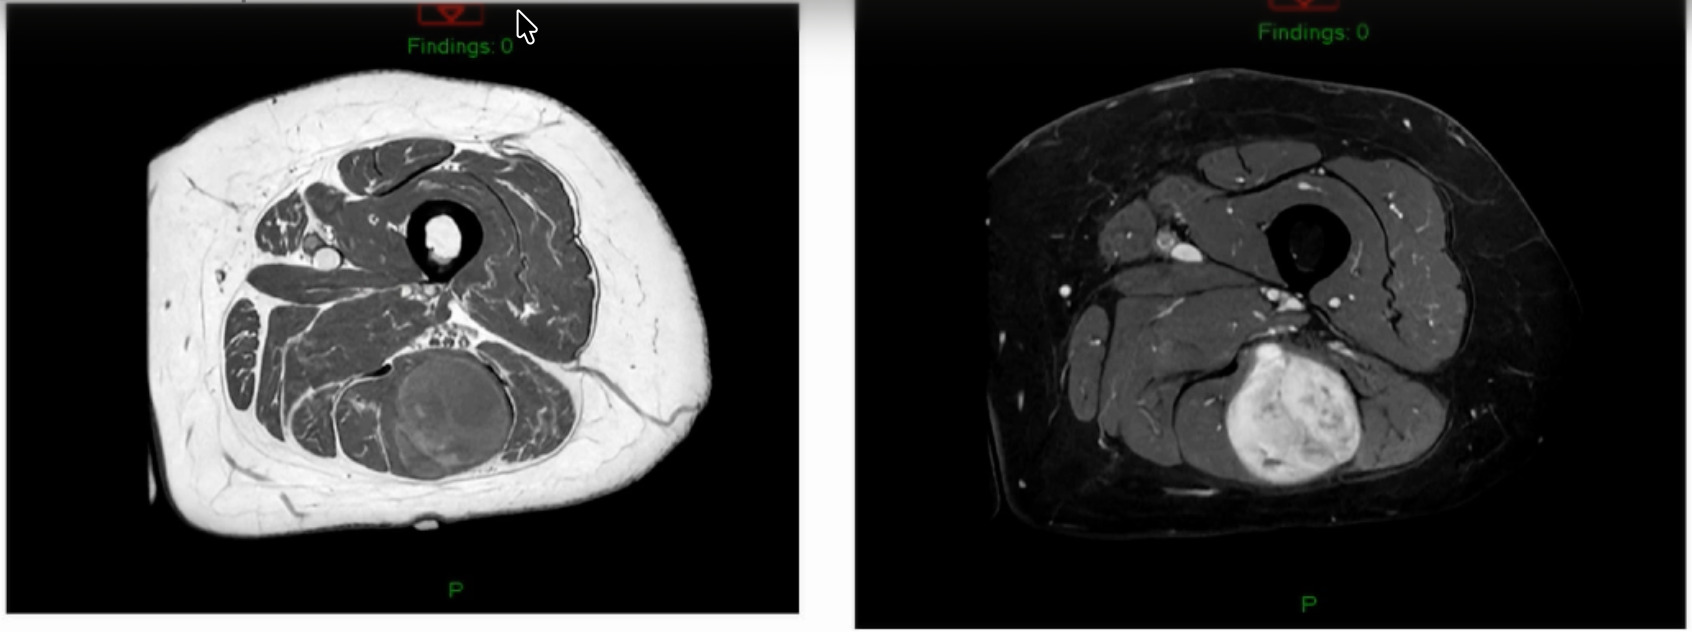

Unsure what it is? Intramuscular lipoma? Intramuscular lipomas aren’t firm and they aren’t hot. Ultrasound for that? The “gold standard” would be an MRI, not an ultrasound, but they did ultrasound it. The ultrasound came back with, “should get an MRI.” But they biopsied it instead. An MRI was then obtained after the biopsy. (Figure 5)

The biopsy came back as a myxoid fibrosarcoma they biopsied it with a needle, so it’s very hard to tell grade. Additionally, if I’ve got a tumor that’s this big and I’ve got a needle the size of a pin then my sampling error is massive. I don’t ever believe grade off of a biopsy. I just get biopsies so that now I can at least give radiation or do whatever pre-operatively. She is starting her radiation next week for a number of reasons. But she’s got a myxoid fibrosarcoma.